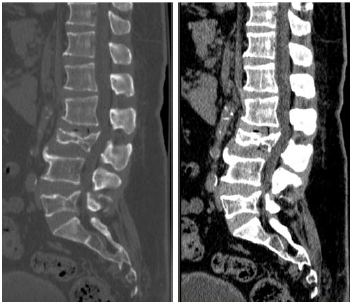

Um paciente de 62 anos de idade foi vítima de queda da própria altura há cerca de três horas. Ele chegou ao pronto-socorro queixando-se de dor lombar de moderada intensidade.

De acordo com a AOOTA spine, é correto classificar a fratura de L3 como do tipo

No caso descrito, foi solicitada uma TC da coluna lombar, conforme apresentado. Esse exame mostra fratura de